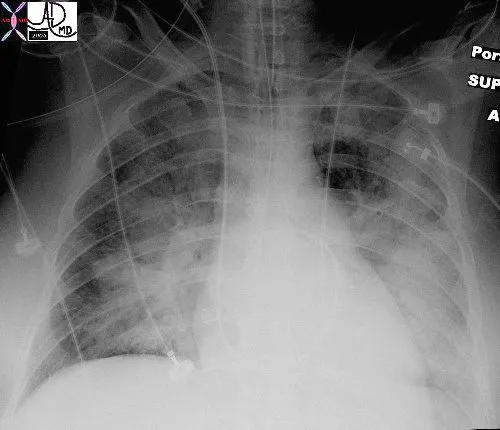

- Chest X-ray (CXR): Key diagnostic tool showing progressive changes.

- Stage 1 (Cephalization): ↑ pressure forces blood to upper lobe vessels.

- Stage 2 (Interstitial Edema):

- Kerley B lines: Short, horizontal lines at lung peripheries.

- Peribronchial cuffing.

- Stage 3 (Alveolar Edema):

- Diffuse, bilateral "batwing" or "butterfly" opacities.

- Pleural effusions, often bilateral.

- Chest X-ray findings include Kerley B lines, cephalization of pulmonary vessels, and a “batwing” appearance.